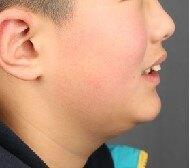

检查:侧貌突,开唇露齿。上颌前突,下颌后缩,上前牙前突10mm左右,咬合深,咬至上颌粘膜,上下牙弓狭窄,牙列拥挤不齐。

通过隐形矫治,序列化推上牙列向后,并适量扩弓,排齐内收上前牙,适量唇倾和片切排齐下前牙。

配合二类牵引,实现咬合跳跃,改善侧貌。